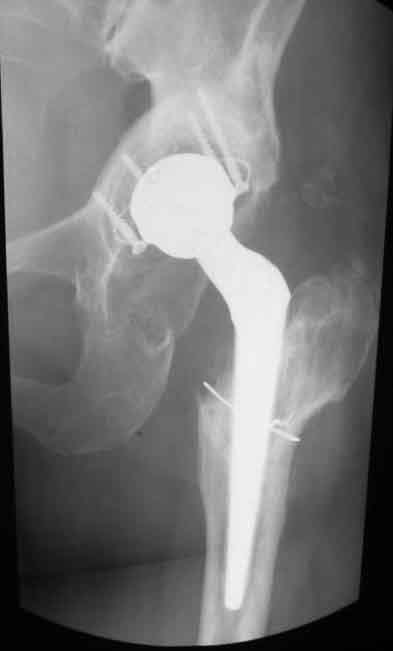

Уважаемые коллеги. Хотелось бы услышать мнения и советы по представляемому случаю. Пациентка 45 лет. Бесцементное эндопротезирование левого тазобедренного сустава 6 лет назад (впадина RM, Mathys, металл-металл, ножка Зульцеровская). За 10 лет до протезирования – коррегирующая остеотомия бедренной кости, которая не срослась в течение года до удаления пластины, а затем срослась в течение 3 месяцев иммобилизации в кокситной повязке. После протезирования получилось наблюдать пациентку почти постоянно, поскольку через 2 года синтезировал ей лодыжки на оперированной стороне, затем, через несколько месяцев удалил фиксаторы, а в 2009г. резецировал мениск на противоположной стороне. Боли все эти годы не беспокоили. Пациентка чуть выше среднего роста, вес тела нормальный. Физические нагрузки переносила хорошо. Работает на 7 этаже без лифта. Год назад экстирпация матки по поводу лейомиомы больших размеров. Несколько месяцев назад появились боли в области левого тазобедренного сустава. При рентгеновском и КТ исследованиях (июль с.г.) – нестабильность тазового компонента. От предложенной замены протеза пациентка на тот момент, слава богу, отказалась. Через какое то время боли в области левого тазобедренного сустава практически полностью прошли, а около 2 месяцев назад появилось ощущение патологической подвижности таза и боли в паху справа, которые через некоторое время уменьшились, а потом снова усилились после значительных физических нагрузок (много ходила по песку на пляже, носила тяжести). Ежедневно принимала диклофенак. На рентгенограммах – переломы правой лонной кости. Сейчас госпитализирована из-за болей в паху справа. Боли слева не беспокоят. На фоне снижения нагрузок в стационаре боли значимо уменьшились. Способна ходить без средств дополнительной опоры.В анализах крови чуть повышены трансаминазы и гамма-ГТ, моча без особенностей.

Вопросы: -правильно ли я расцениваю переломы как стрессовые на фоне неполноценного таза (pelvic insufficiency stress fractures)? -Можно ли так же расценить ситуацию на стороне протеза и, соответственно, не торопиться с ревизией, рассчитывая на вторичную стабилизацию? Уж больно не хочется менять ножку. -Если думать о ревизии, то когда? На представленных снимках тазобедренный сустав до и сразу после операции, затем 2 снимка 2009г., когда ничего не беспокоило, затем КТ 2-х месячной давности и вчерашние рентгенограммы обоих тазобедренных суставов.

Сергей, очень возможно, что перелом и стрессовый, но мне видится, что его причина в нестабильности чашки. Дело в том, что в отличии от ножек, чашка при своей дестабилизации болит гораздо меньше и больные терпят до последнего.

При сравнении рентгенограмм можно увидеть насколько чашка переместилась от места своего первичного расположения. От опрокидывания ее удерживают конструкционные элементы "рожки". Без них ситуация, возможно, уже была бы катастрофической (чашка в тазу). Думаю надежды на вторичную интеграцию, могут быть обмануты и ревизии не избежать.

Если внимательно посмотреть на рентгеновские снимки, то видно, что пара трения действительно металл-металл.